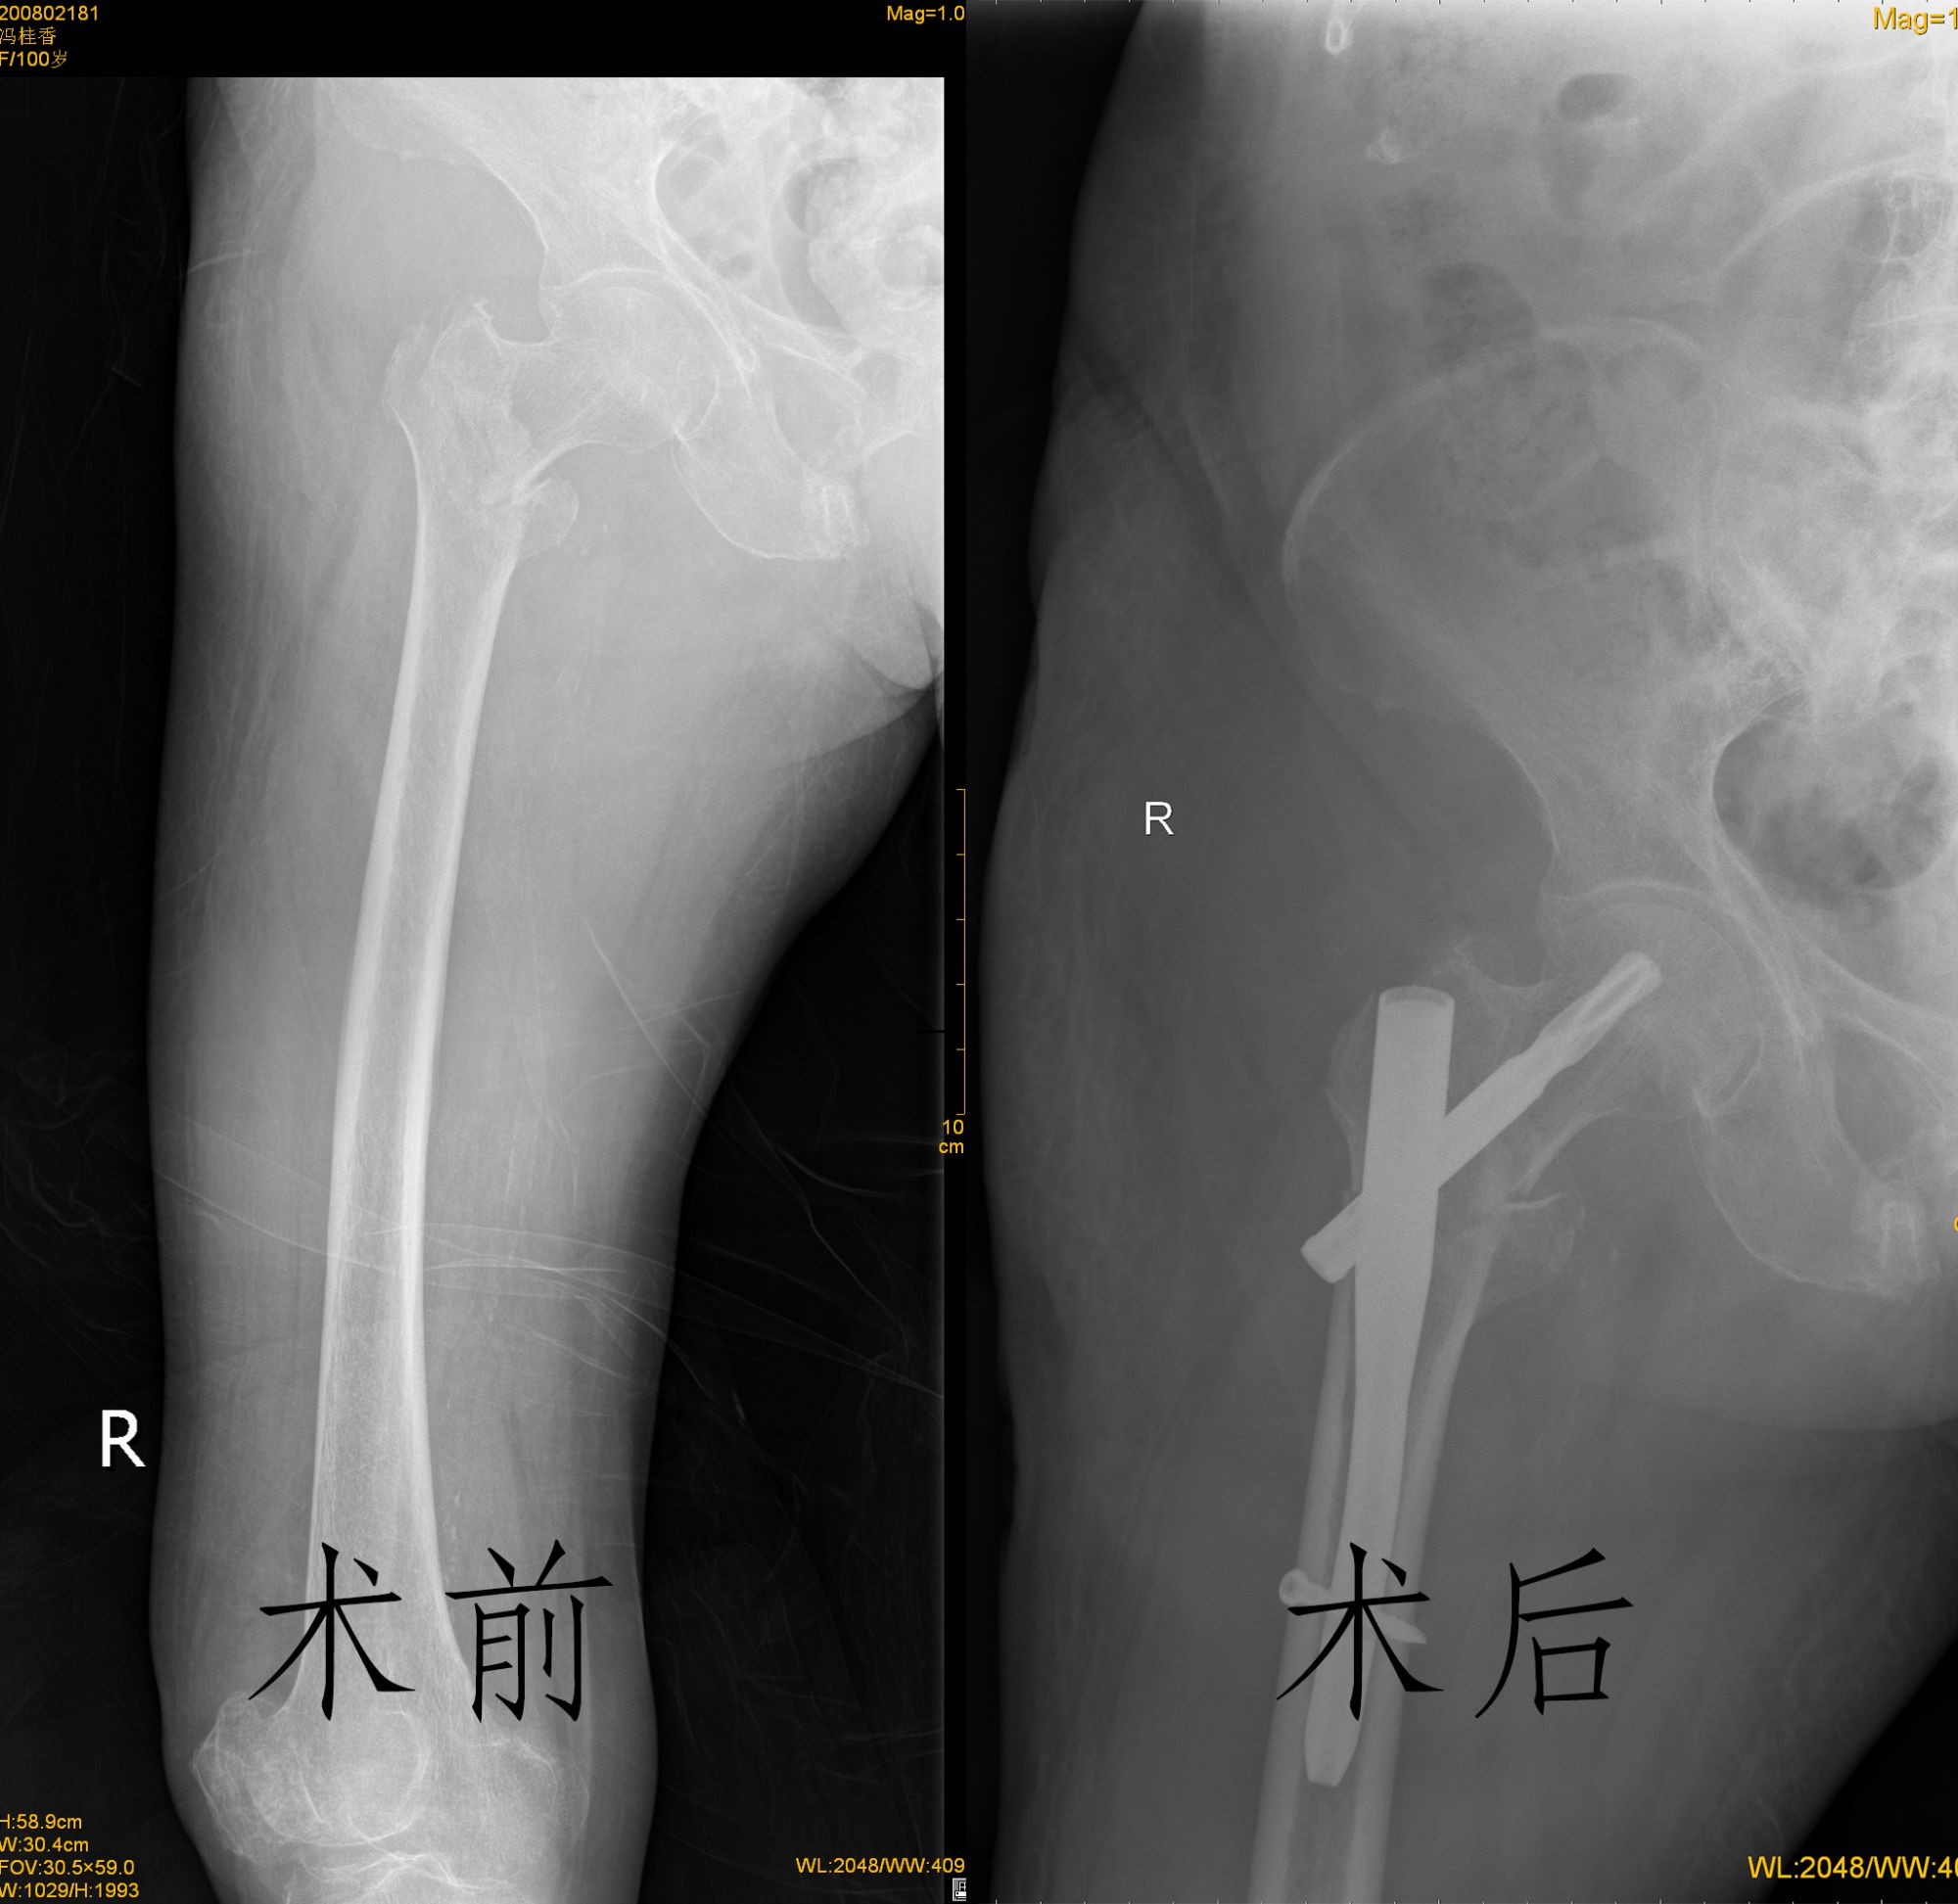

冯奶奶在家中活动时不慎摔倒,当时便感觉右髋部疼痛难忍,瘫卧在地,家人立刻联系某医院,但因高龄遭到婉拒。看着冯奶奶在床上的痛苦表情,家属不忍心放弃治疗,来我院咨询。冯奶奶既往有冠心病、心梗等病史,拍片显示右侧股骨转子间骨折,骨科一病区徐宝友主任了解情况后,决定给予手术治疗。经过各相关专业会诊,进行充分的术前评估,制定了细致的麻醉手术治疗方案。8月4日,在腰硬联合复合神经阻滞麻醉下为百岁老人行股骨转子间骨折闭合复位PFNA内固定术,该技术具有微创、创伤小、出血少等优势,在麻醉科手术室的大力配合下,手术非常顺利,术后恢复良好,已顺利出院。